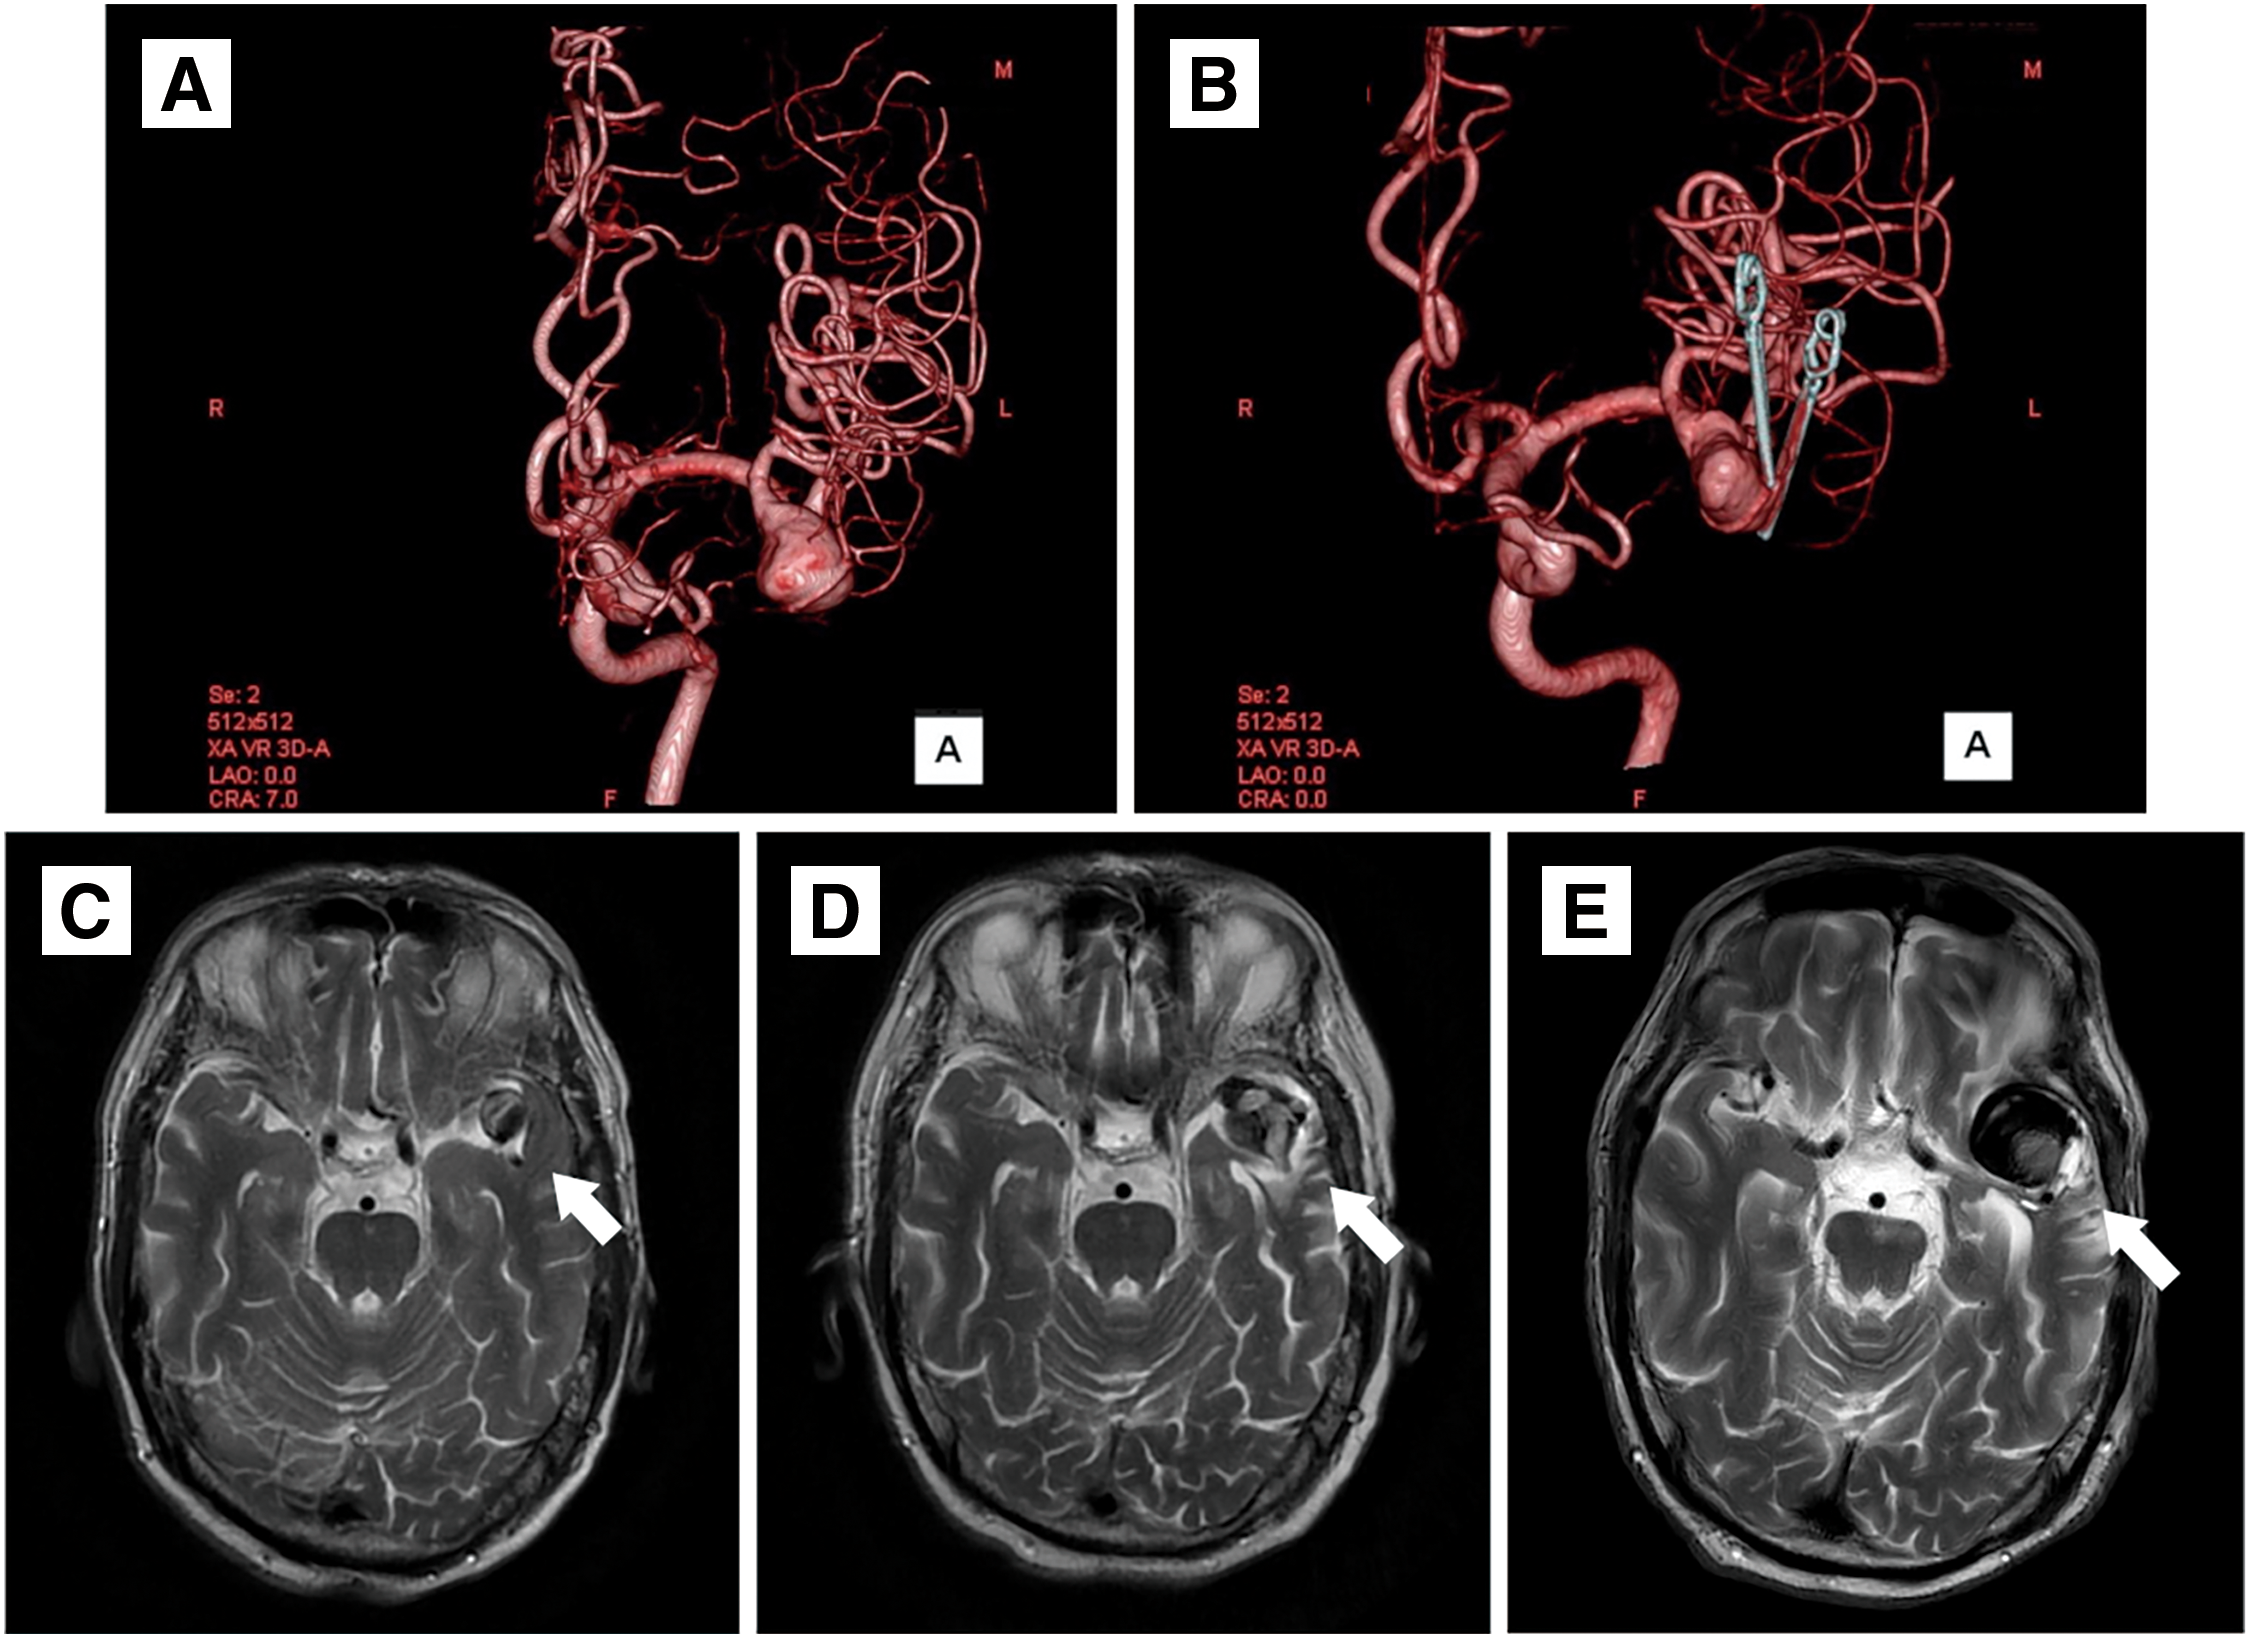

A 72-year-old man was referred to our hospital for a left MCA large aneurysm on MRI, which was associated with transient left visual field disorder. Angiography revealed a 15-mm diameter aneurysm (Fig. 1A). The MCA aneurysm was clipped partially, due to the presence of significant arteriosclerosis (Fig. 1B). The residual aneurysm gradually increased in size (Fig. 1C–1E). Two years after the clipping, he started taking 100 mg/day aspirin because of amaurosis fugax on the left side. Four years after the clipping, he developed cerebral infarction in the left MCA territory and was treated at a different hospital (Fig. 2A and 2B). A closer MRI revealed thrombosis within the aneurysm, leading to a diagnosis of cerebral embolism due to thrombus in the aneurysm. The patient was also added with clopidogrel 75 mg/day. Eight years after the clipping, another stroke occurred in the left MCA territory, resulting in dysarthria and motor aphasia (Fig. 2C and 2D). Because the aneurysm continued to gradually increase in size, the patient was referred to our hospital 8 years after the clipping. Cerebral angiography revealed the large left MCA aneurysm with a maximum dome diameter of 13 mm (Fig. 3A and 3B), and the left M2 superior trunk was occluded. The maximum dome diameter of the aneurysmal measured on MRI was 27 mm, and the majority of the aneurysm was thought to be thrombosed (Fig. 3C). Although the patient did not show symptoms related to the mass effect of the thrombosed aneurysm, repeated cerebral infarctions developed due to intra-aneurysmal thrombosis, despite dual antiplatelet therapy (DAPT), indicating the need for surgical intervention. The left M2 had only 1 inferior trunk due to occlusion and had developed into a sidewall aneurysm, which made FD placement more favorable. Therefore, FD placement was performed in the same year.